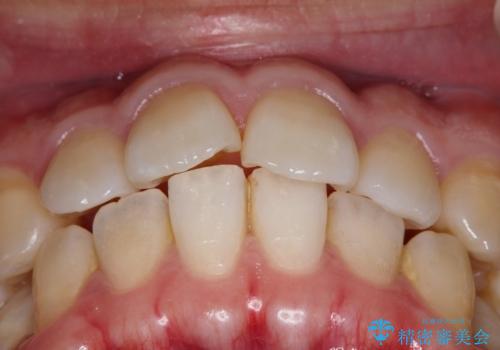

- 上の歯が出ているのが気になるのを主訴にご来院されました。人前で話すお仕事をされており目立たないマウスピース治療を希望されていました。

上の前歯が出ているという主訴が綺麗に改善されました。

その他の部位のがたつき、奥歯の噛み合わせも以前と比べると良くなっています。